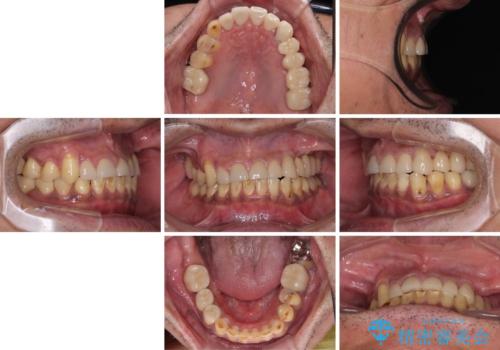

矯正治療は想定通り長期化しましたが、しっかりと奥歯の咬み合わせを向上させて前歯の被蓋を改善させることができました。

目立つ銀歯やすり減った前歯がセラミッククラウンとなり、患者様には大変満足していただけました。